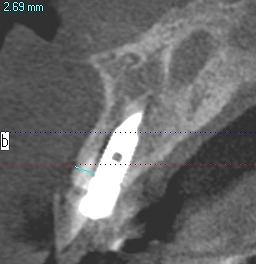

埋入時のCTになります

イメージ通りの埋入につながっています

インプラントは4mmの13mmという長さのインプラントを埋入しています